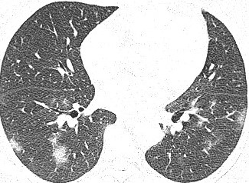

Radiographic findings

พบความผิดปกติจากภาพถ่ายรังสีทรวงอกในวันแรกที่รับไว้ในโรงพยาบาล 66% โดยส่วนใหญ่ที่พบเป็น bilateral peripheral opacities/consolidations (รูปที่ 1) มีส่วนน้อยที่เป็น unilateral involvement (รูปที่ 2) บางรายพบลักษณะของ focal opacities ทำให้ดูคล้ายเป็น nodule หรือ mass (รูปที่ 3) และพบ pleural effusion (รูปที่ 4) เพียง 3 รายเท่านั้น ได้ทำการตรวจ CT scan ไป 4 ราย ซึ่งพบว่ามีความไวในการตรวจพบความผิดปกติได้เพิ่มขึ้น

รูปที่ 2. แสดงภาพถ่ายรังสีทรวงอกธรรมดา (ซ้ายมือ) และคอมพิวเตอร์ (ขวามือ) ของผู้ป่วยวันที่ 4 หลังเริ่มมีอาการติดเชื้อโควิด-19 พบลักษณะ unilateral (left) peripheral opacity/consolidation